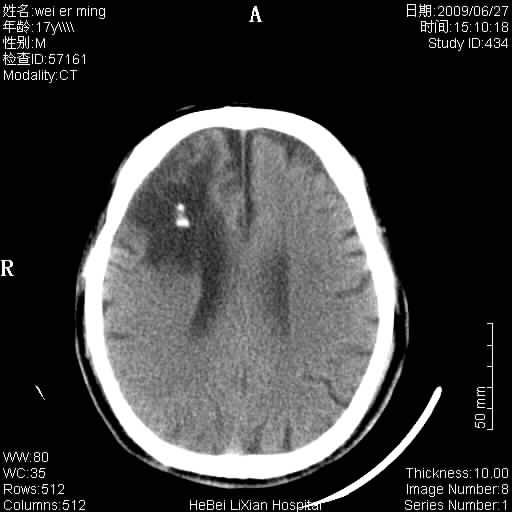

标题: CT20838:帮忙看看,是软化灶吗?

患者,男,67岁.既往有脑血栓病史.若是软化灶里面怎么出现钙化呢?

周围没有水肿,没有占位;结合病史考虑为软化灶,钙化。

支持 右侧额叶软化灶伴脑穿通畸形(钙化为胶质增生、机化、钙化)。

是脑软化灶,其内的钙化可解释为闭塞血管内的血栓钙化。

脑梗塞后形成的软化灶内可以有钙化密度影,系血管出血机化或血管内血栓钙化所致。